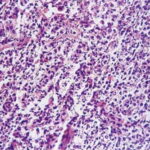

Histopathology . Pyoderma gangrenosum exhibits a dichotomous tissue reaction, showing central necrotizing suppurative inflammation, usually with ulceration, and a peripheral lymphocytic vascular reaction comprising perivascular and intramural lymphocytic infiltrates, usually without fibrin deposition or mural necrosis . Transitional areas show neutrophils in a loose cuff around the angiocentric lymphocytic infiltrates, defining a mixed lymphocytic and neutrophilic vascular reaction termed a Sweet’s-Iike vascular reaction . Bullous lesions may also demonstrate a Sweet’s-like vascular reaction with perivascular disintegrating neutrophilic infiltrates and hemorrhage without mural necrosis or luminal fibrin deposition. At variance with Sweet’s syndrome is destruction of the connective tissue framework with resultant tissue pathergy . Although a leukocytoclastic vasculitis may be observed in areas of maximal tissue pathology, pyoderma gangrenosum does not reflect a primary vasculitis . In some cases a necrotizing pustular follicular reaction may be the central nidus of the lesion, particularly in the vesicular pustular variant associated with ulcerative colitis or hepatobiliary disease. In the superficial granulomatous variant, florid pseudoepitheliomatous hyperplasia may be observed along with the intraepithelial and superficial dermal suppurative granulomatous inflammation with admixed plasma cells and eosinophils . Gases of pyoderma gangrenosum associated with Grohn’s disease may have areas of granulomatous inflammation . |